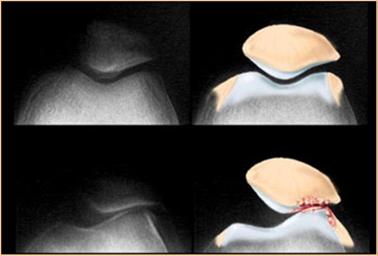

Boczne przyparcie rzepki (ELPS) to najprościej mówiąc nadmierne przesunięcie rzepki w stronę boczną, do którego dochodzi podczas ruchów kolana. Rzepka zamiast poruszać się prawidłowo po bloczku kości udowej w trakcie zgięć i wyprostów kolana przesuwa się do boku.

Rzepka to mała, płaska, trójkątna kość zlokalizowana z przodu stawu kolanowego. Jest osadzony w ścięgnie mięśnia czworogłowego uda, czyli grupy mięśni znajdujących się w przedniej części uda. Rzepka znajduje się bezpośrednio nad dystalnym końcem kości udowej, tworząc staw zwany stawem rzepkowo-udowym.

Rzepka przyczynia się do dźwigni i wydajności mięśni czworogłowych, umożliwiając efektywne wyprostowanie nóg i pomagając w ruchach, takich jak chodzenie, bieganie i skakanie.

Dolegliwości wpływające na rzepkę lub staw rzepkowo-udowy, takie jak zwichnięcie rzepki lub zespół bólowy rzepkowo-udowy, mogą wpływać na funkcję kolana i mogą wymagać oceny lekarskiej i leczenia.

Poza widocznymi objawami związanymi z nieprawidłowym ruchem rzepki ELPS charakteryzuje się bólem lub sztywnością zazwyczaj w przednio – bocznej części kolana. Pacjenci skarżą się na dolegliwości bólowe związane z długim siedzeniem, a także podczas klękania, biegania, chodzenia po schodach i kucania. Bardzo ważne jest by jak najwcześniej rozpocząć indywidualnie dobrane ćwiczenia i zabiegi. Nie leczone boczne przyparcie rzepki może doprowadzić do chondromalacji, czyli uszkodzeń chrząstki stawu rzepkowo-udowego. Z czasem zwiększa się również ryzyko zwichnięcia rzepki.